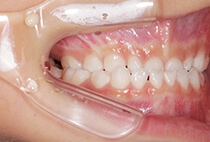

20代女性の患者さま。

八重歯の見た目が気になってご来院されましたが、実は顎の痛みや開口障害など、顎関節症の症状もありました。

そのため、かみ合わせと顎関節症の治療を同時に行ったにもかかわらず、2年間で治療が終了。

かみ合わせが整い咬筋の過緊張も改善しました。咬筋の肥大も治ってフェイスラインがすっきりしました。

最終的には美しい歯並びと、安定した痛みのないかみ合わせが実現しました。

八重歯が気になる

叢生、顎関節症、開口障害

しっかり前歯を下げるために、インプラントアンカーを使用してコントロールしました。

かみ合わせが整うと咬筋の過緊張が改善。

過緊張による筋肉肥大も改善しフェイスラインもすっきりしました。

治療前

治療後